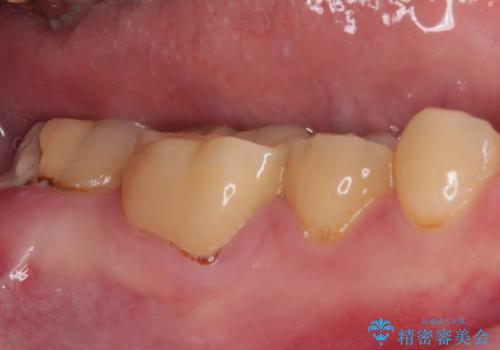

- 東南アジアへの長期赴任を前に、以前から気になっていたむし歯を治療したいとのことで来院された患者様です。

レントゲン写真から、神経の近くにまでむし歯が及んでいる様子が分かり、範囲も広範囲であったので、まずは仮歯に置き換え、その後オールセラミッククラウンにて補綴治療を行うこととしました。

処置を開始するに当たり検査診断を行ったところ、歯髄組織にまでむし歯が及んでいる可能性が示唆されたため、万が一の事態に備えてラバーダム装着による無菌的環境にて虫歯除去を行うこととしました。